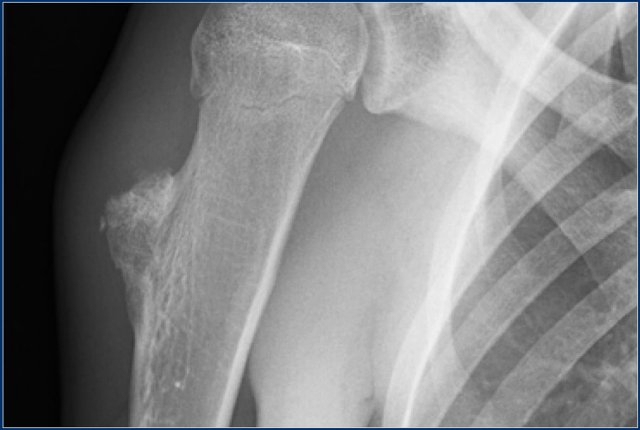

Here a patient with a juxtacortical sclerotic mass of the proximal humerus (left).

This proved to be a reactive calcification secondary to trauma.

Notice the resemblance to a juxtacortical mass in another patient (right), which was a biopsy proven parosteal osteosarcoma.

This shows that differentiating a tumor from a reactive proces scan be quite difficult in some cases.

When a reactive process is more likely based on history and imaging features, follow-up is sometimes still needed.